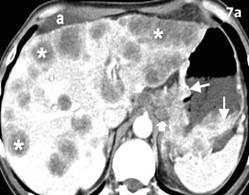

♦ Evidencia radiológica de neumoperitoneo compatible con ruptura de víscera

♦ Evidencia de una rotura diafragmática

♦ Hemorragia gastrointestinal significativa y persistente observada en el drenaje nasogástrico o en el vómito.

Control de daños